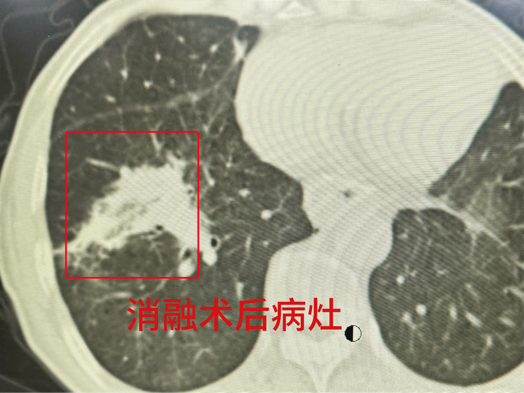

在麻醉团队的全力保障下,陶冀教授团队凭借丰富的临床经验和精湛的技术,采取左侧卧位,运用单针精准分段穿刺技术,如同一位技艺高超的工匠,将消融针尖精准无误地置入病灶核心。术中,他们以30—40W的中低功率进行消融,持续9分钟后,谨慎退针并补充消融,通过两个精心设计的消融循环,确保消融范围完全覆盖病灶,实现肿瘤的彻底灭活。手术过程顺利,术中无出血,仅出现少量气胸,经置管抽气后迅速缓解,重要血管与支气管均得到妥善保护。

本次手术的成功,实现在多重高危条件下的关键突破。在高龄、多发癌、全身衰弱、心脏功能不全等复杂病情的基础上,成功攻克肺血管池内高风险转移灶这一治疗禁区,以微创的方式为患者带来确切的疗效。这一成果不仅为同类晚期、超高龄、无法耐受常规抗肿瘤治疗的患者提供可复制、安全有效的救治新模式,更充分展现哈医大肿瘤医院消融团队在高危复杂肿瘤微创治疗领域的领先水平,为更多患者带来生的希望。